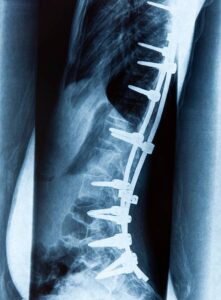

FAILURE OF A SPINAL IMPLANT OR HARDWARE

Unfortunately, spinal implant failure is a very real and serious risk. When these devices, which are designed to support and stabilize the spine malfunction, the consequences can be severe. Loosening, fracture, or dislodgement can lead to nerve compression, chronic pain, and limited mobility. In these cases, revision surgery, with its challenges and uncertainties, becomes necessary to correct the problems and restore function.

The most common spinal implants include pedicle screws, rods, interbody cages, and artificial discs. These devices are utilized in procedures such as spinal fusion for Scoliosis Surgery or disc replacement. Specifically, they address conditions like degenerative disc disease, spinal stenosis, and fractures.

Hardware Failure

The fusion hardware could fail if subjected to undue stress, such as lifting heavy objects or engaging in sports too soon after surgery. The hardware might break shortly after surgery or over time if the fusion doesn’t set properly. Implant failures pose several risks, including pain, instability, nerve compression, and a potential need for additional surgery. In some cases, implant failures can lead to complications such as adjacent segment degeneration. This is where stress on adjacent vertebrae increases, requiring further interventions.

Failed spinal hardware occurs when the rods or screws used to hold together fused sections of the spine fatigue and break. This condition often describes patients who haven’t had a successful outcome following back or spine surgery, continuing to experience pain due to implant failure.